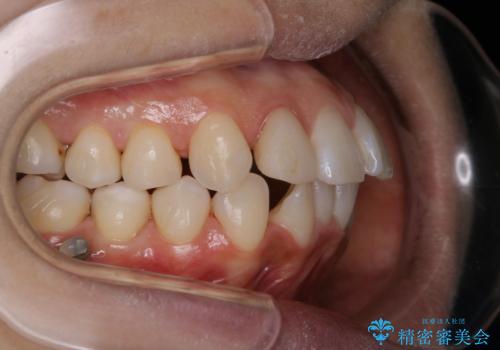

- インビザラインでのマウスピース矯正中の方です。歯についてしまったステインが気になり綺麗にしたいとのことでした。PMTC60分コースを行いました。

PMTC(保険外治療)は、毎日の歯磨きで落としきれない汚れや、コーヒ、紅茶・タバコのヤニなどの着色も除去します。目には見えない歯と歯の間・歯肉の境目・インビザライン中はアタッチメント周囲などに残っているプラーク(歯垢)もしっかり取り除きます。PMTCでは専門的な機械や材料を使用して、徹底的に汚れを除去するため、虫歯・歯周病・口臭予防などにつながります。

またPMTCを行うことで、ご自身本来の歯の色になり自然な明るさになります。